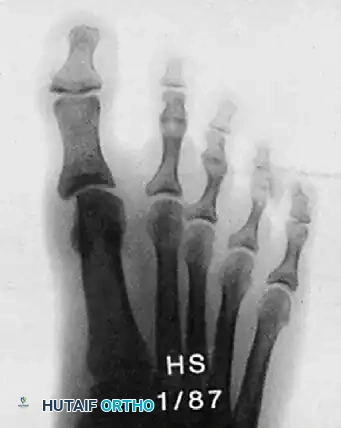

Hutaifortho's Operative Orthopaedics 12th Ed

Updated: Apr 2026